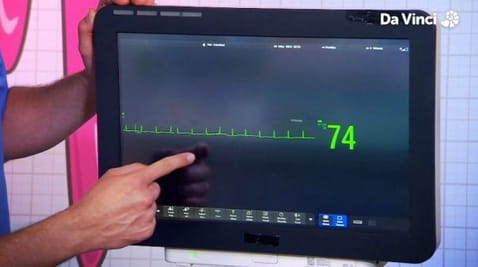

2. Niesamowita pompa serca